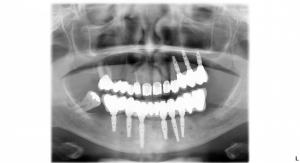

Po zahojení zubných implantátov, ktoré trvalo tri mesiace sa pacientka vrátila na kliniku a začalo sa s vrchnou čeľusťou. Pacientke bola urobená endodoncia – ošetrenie koreňového kanálika. Zuby sa obrúsili do požadovaného tvaru a pripravili sa na nasadenie koruniek. Nasledovalo odobratie odtlačkov zubných implantátov a obrúsených zubov. Výroba zubných koruniek v zubnom laboratóriu trvala tri týždne. Posledná návšteva pacientky na klinike bola na nasadenie trvalých koruniek. Ponúkame Vám fotografie pacientky po ukončení ošetrenia a snímky pred a po ošetrení.